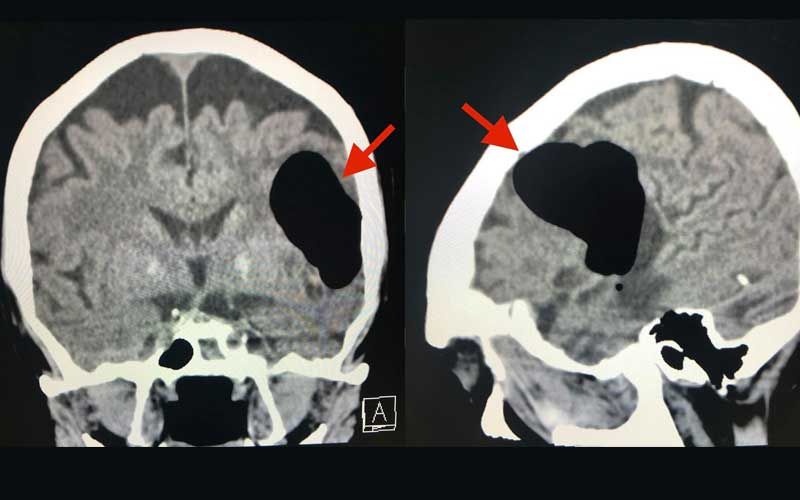

วันที่ 14 พฤษภาคม 2563 ผู้ ป่ ว ย กลับมา รพ.อีกครั้งหลังจากจามแล้วเอามือปิดปากปิดจมูกเพราะไม่อย ากให้มีเสียงดัง หลังทำมีอาการพูดไม่ชัด หน้าข้างขวาเบี้ยว หูข้างซ้ายอื้อ มีเสียงดัง ทำคอมพิวเตอร์ ส ม อ ง พบลม (air pocket) ในเนื้อ ส มอ ง ข้างซ้ายขนาด 5.1 × 4.1 × 2.8 เซนติเมตร (ดูรูป) ตำแหน่งเดิมเหมือนเมื่อ 3 ปี 5 เดือนก่อน แต่ปริมาตรของลมในเนื้อสมองครั้งนี้น้อยกว่า ผู้ ป่ ว ย น อนในโรงพย าบาล 4 วัน อาการดีขึ้นช้าๆ กลับบ้านได้